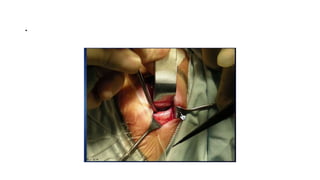

Inferior orbital decompression

• Done through subciliary,

transconjuctival or Caldwell-Luc

incision or combined approach

• A skin-muscle flap is elevated in the

lower eyelid and the orbital rim is

visualized

• The periosteum is incised and